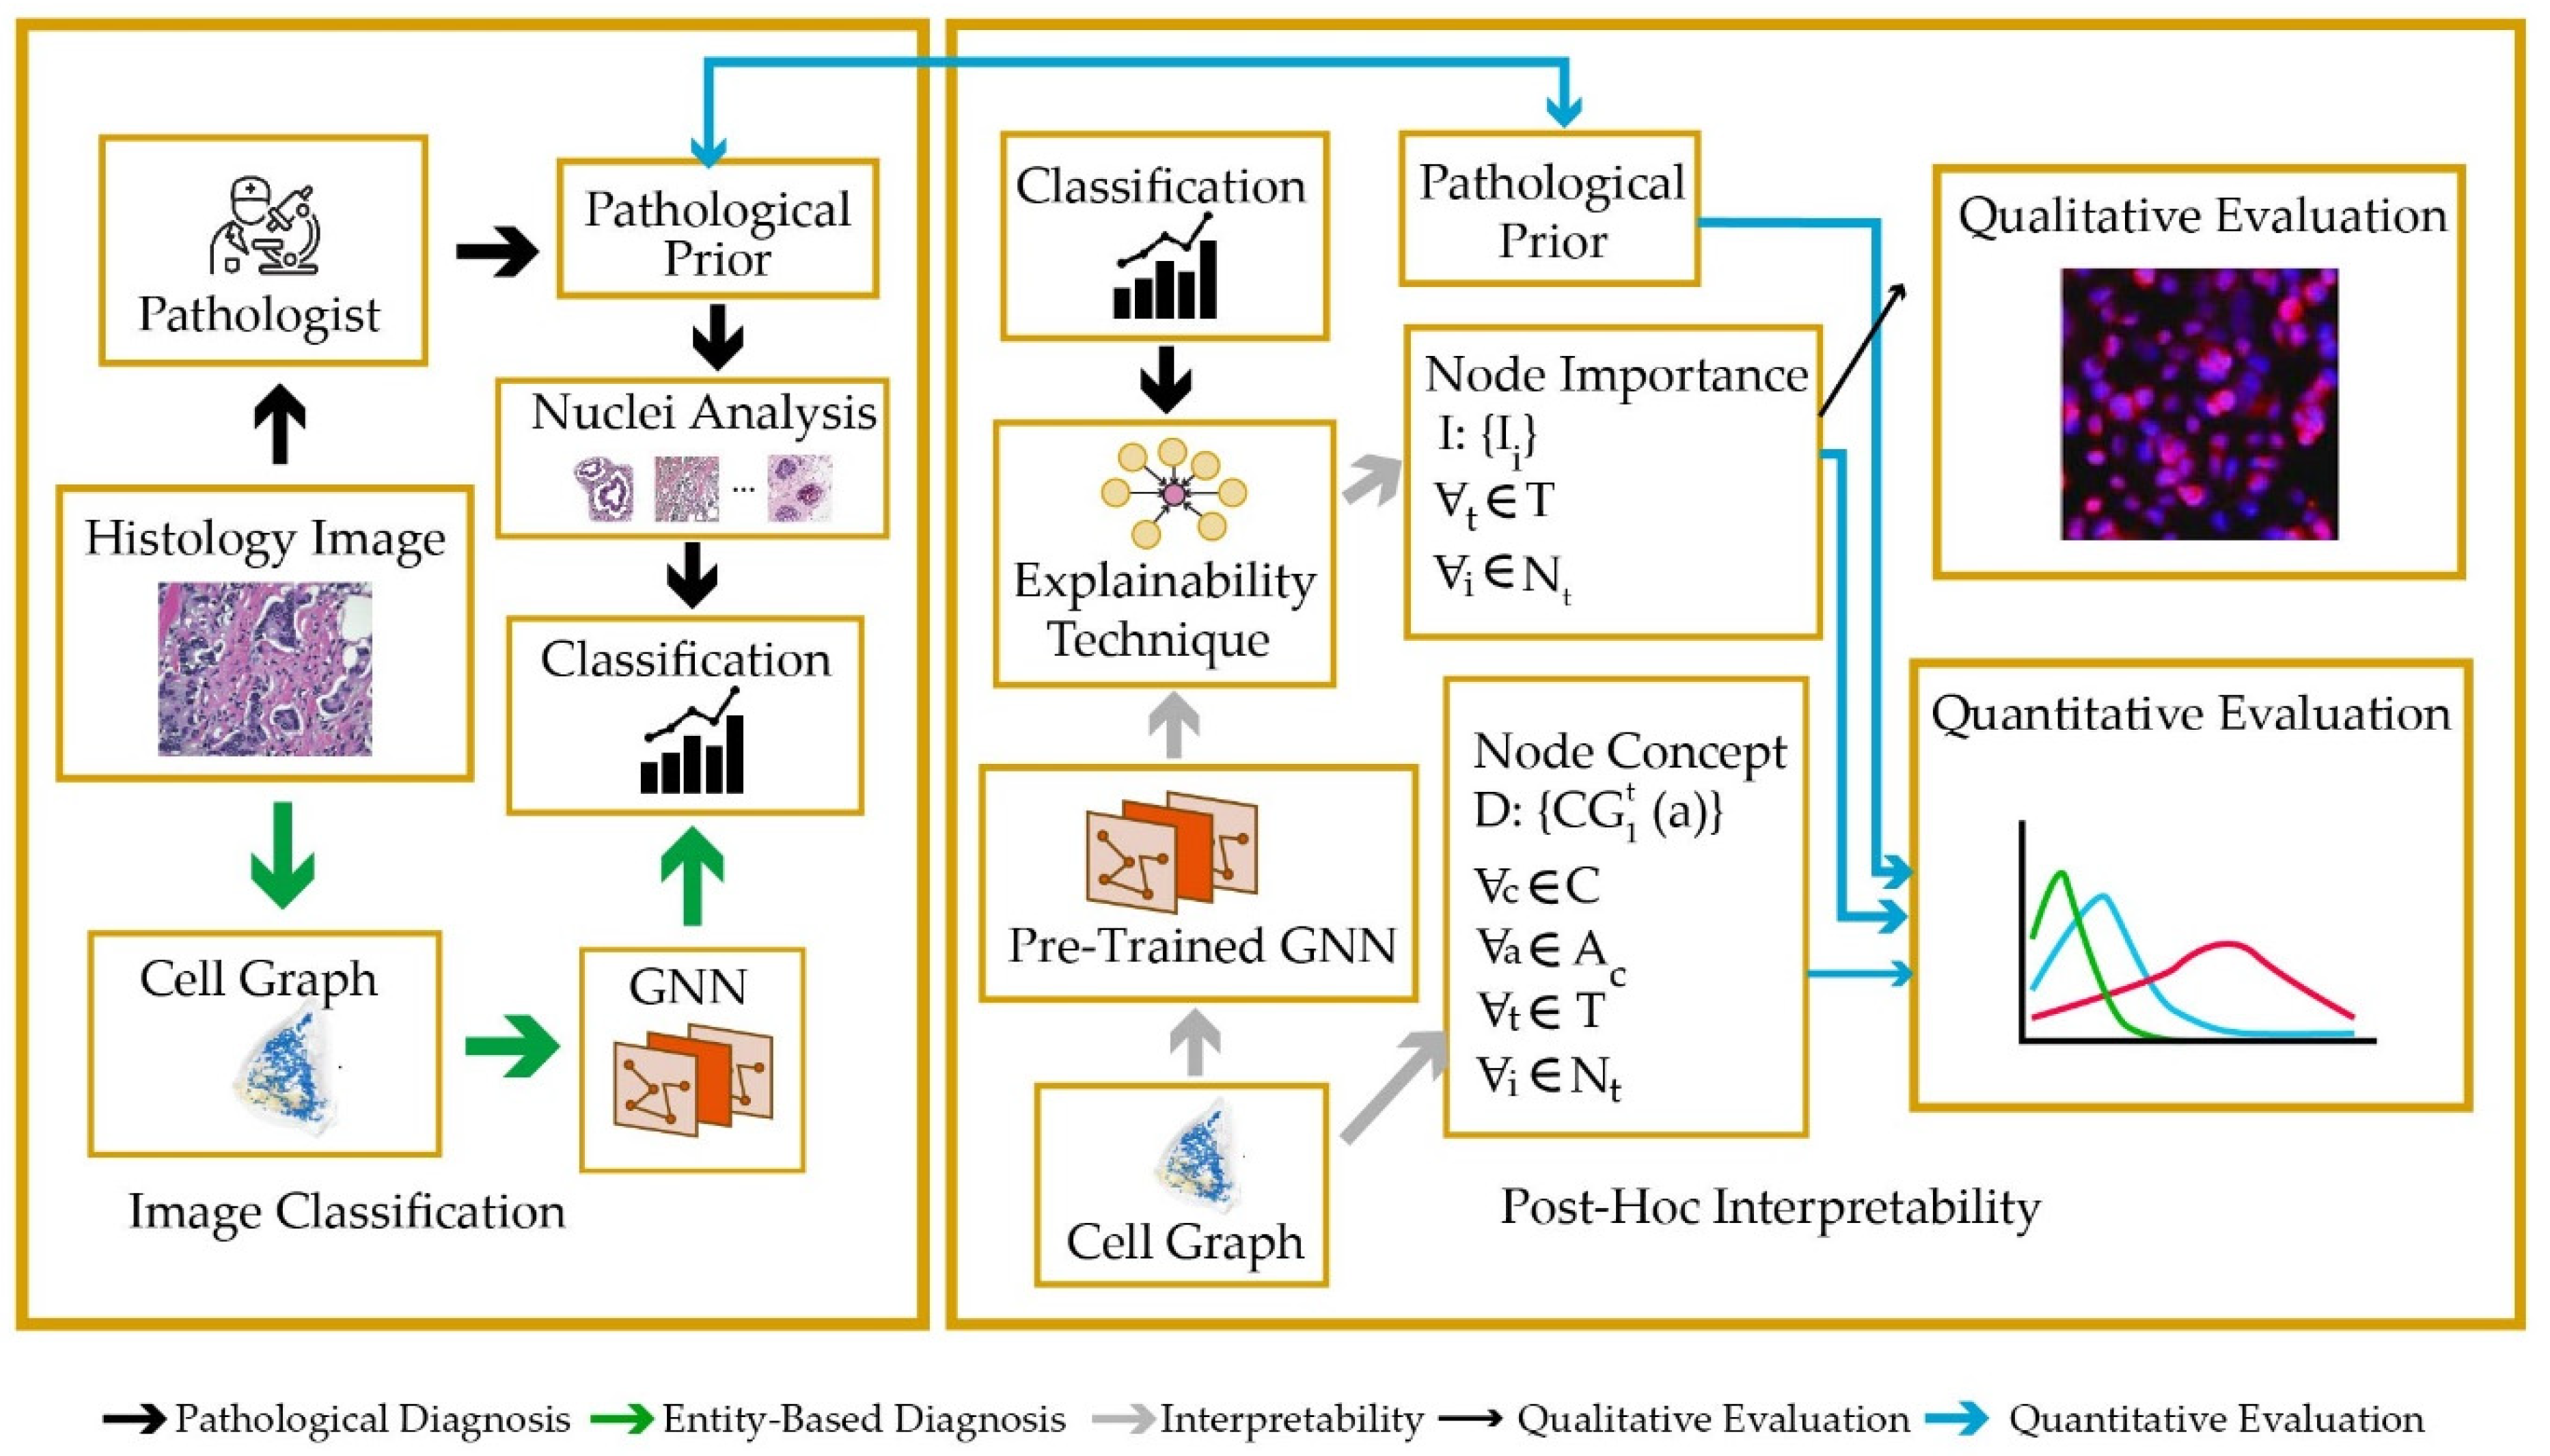

Data That Shows Early Detection Rather Than Late Detection In Breast Cancer

Build inspiration with our stunning architectural Data That Shows Early Detection Rather Than Late Detection In Breast Cancer collection of extensive collections of structural images. structurally highlighting photography, images, and pictures. perfect for architectural portfolios and presentations. Our Data That Shows Early Detection Rather Than Late Detection In Breast Cancer collection features high-quality images with excellent detail and clarity. Suitable for various applications including web design, social media, personal projects, and digital content creation All Data That Shows Early Detection Rather Than Late Detection In Breast Cancer images are available in high resolution with professional-grade quality, optimized for both digital and print applications, and include comprehensive metadata for easy organization and usage. Discover the perfect Data That Shows Early Detection Rather Than Late Detection In Breast Cancer images to enhance your visual communication needs. Cost-effective licensing makes professional Data That Shows Early Detection Rather Than Late Detection In Breast Cancer photography accessible to all budgets. The Data That Shows Early Detection Rather Than Late Detection In Breast Cancer archive serves professionals, educators, and creatives across diverse industries. Time-saving browsing features help users locate ideal Data That Shows Early Detection Rather Than Late Detection In Breast Cancer images quickly. Each image in our Data That Shows Early Detection Rather Than Late Detection In Breast Cancer gallery undergoes rigorous quality assessment before inclusion.